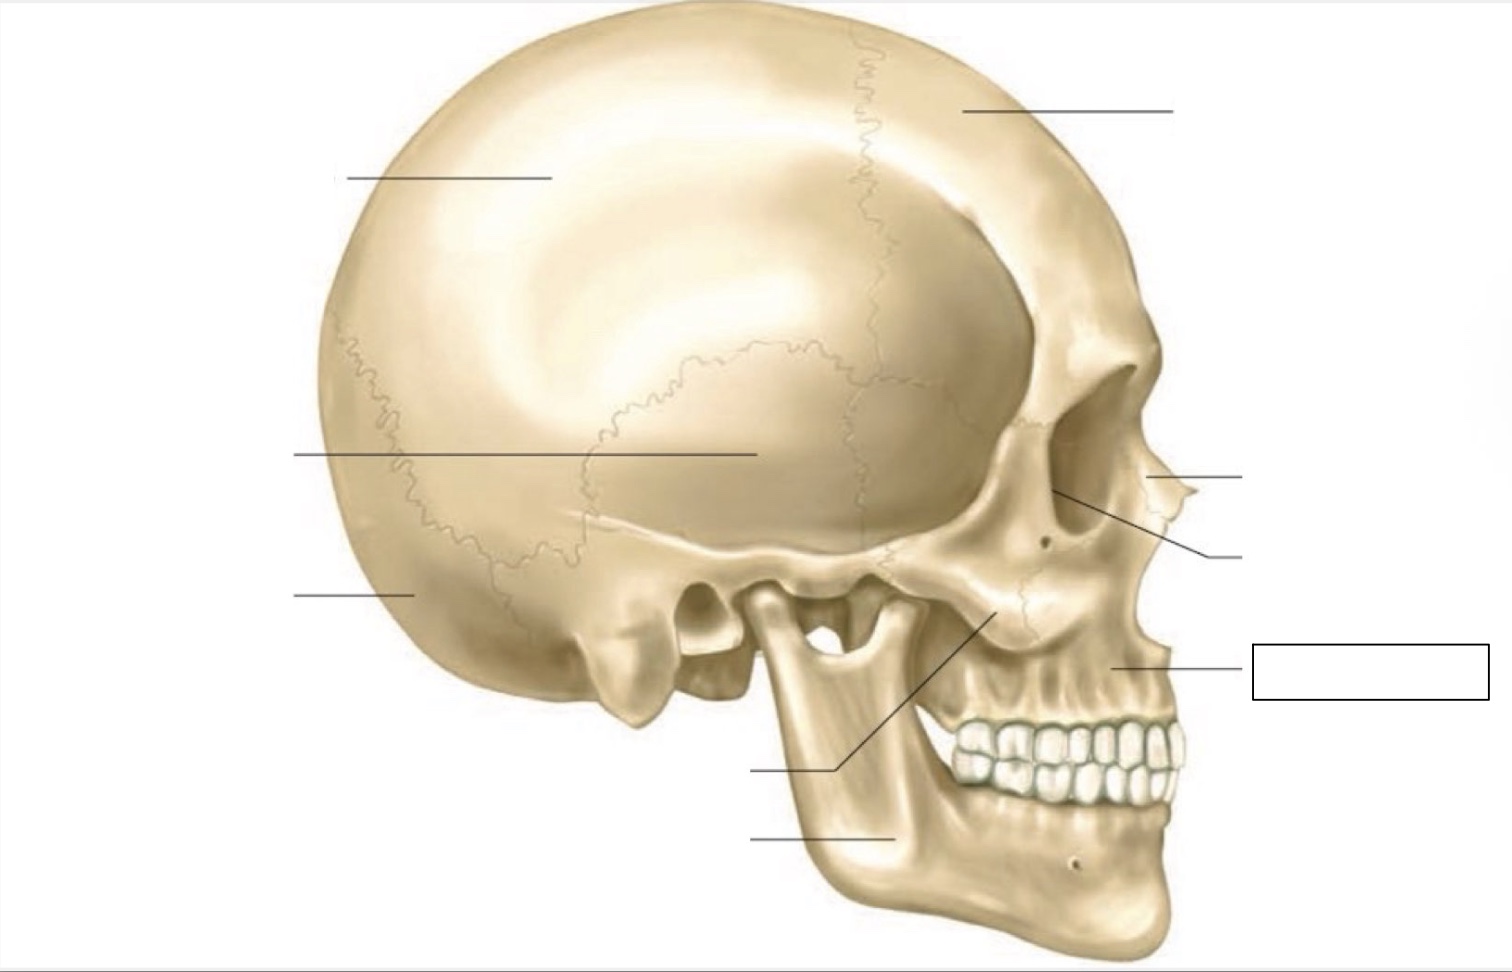

skull

frontal bone

nasal bone

orbit

maxilla

mandible

zygomatic bone

occipital bone

temporal bone

parietal bone